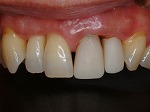

~術前~

オールセラミック修復

~術後~